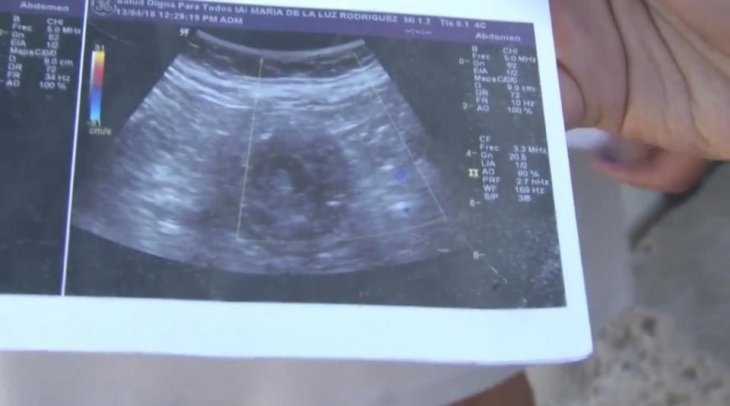

70-річна пенсіонерка оголосила про вагітність і претендує на рекорд

70-річна мексиканка Марія де ла Луз заявила про те, що перебуває на шостому місяці вагітності. Жінка представила знімки УЗД, але поки не задокументувала документ для встановлення рекорду.

"Мені сказали, що це дівчинка. Подивіться, на знімку видно її маленьке личко", - розповіла вона виданню Daily Mail.